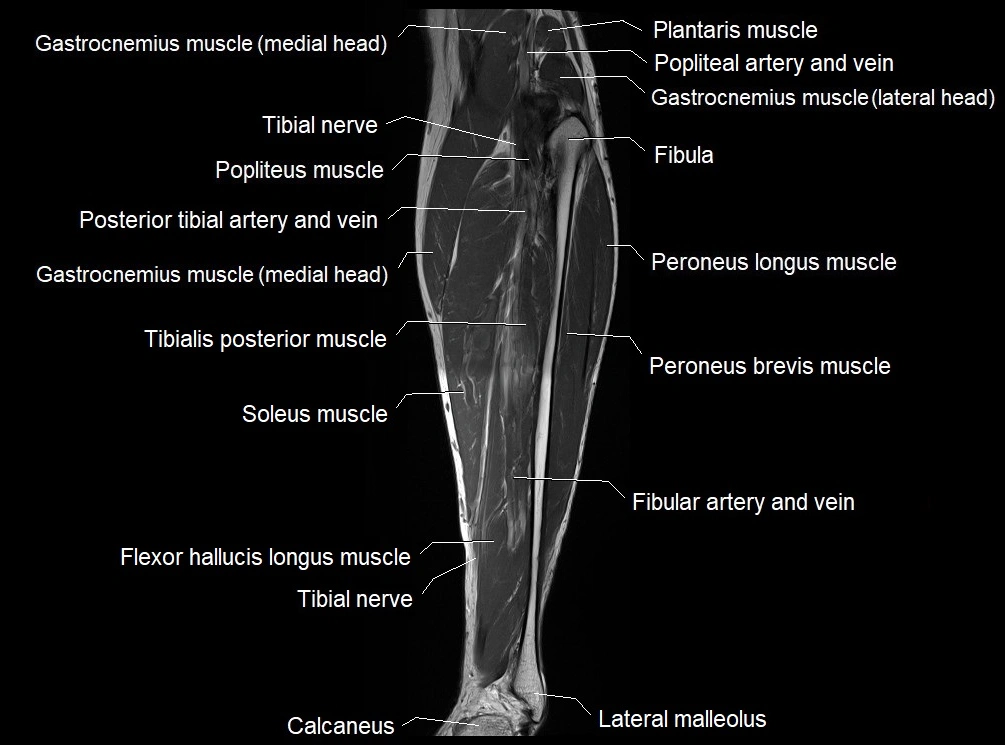

MRI image